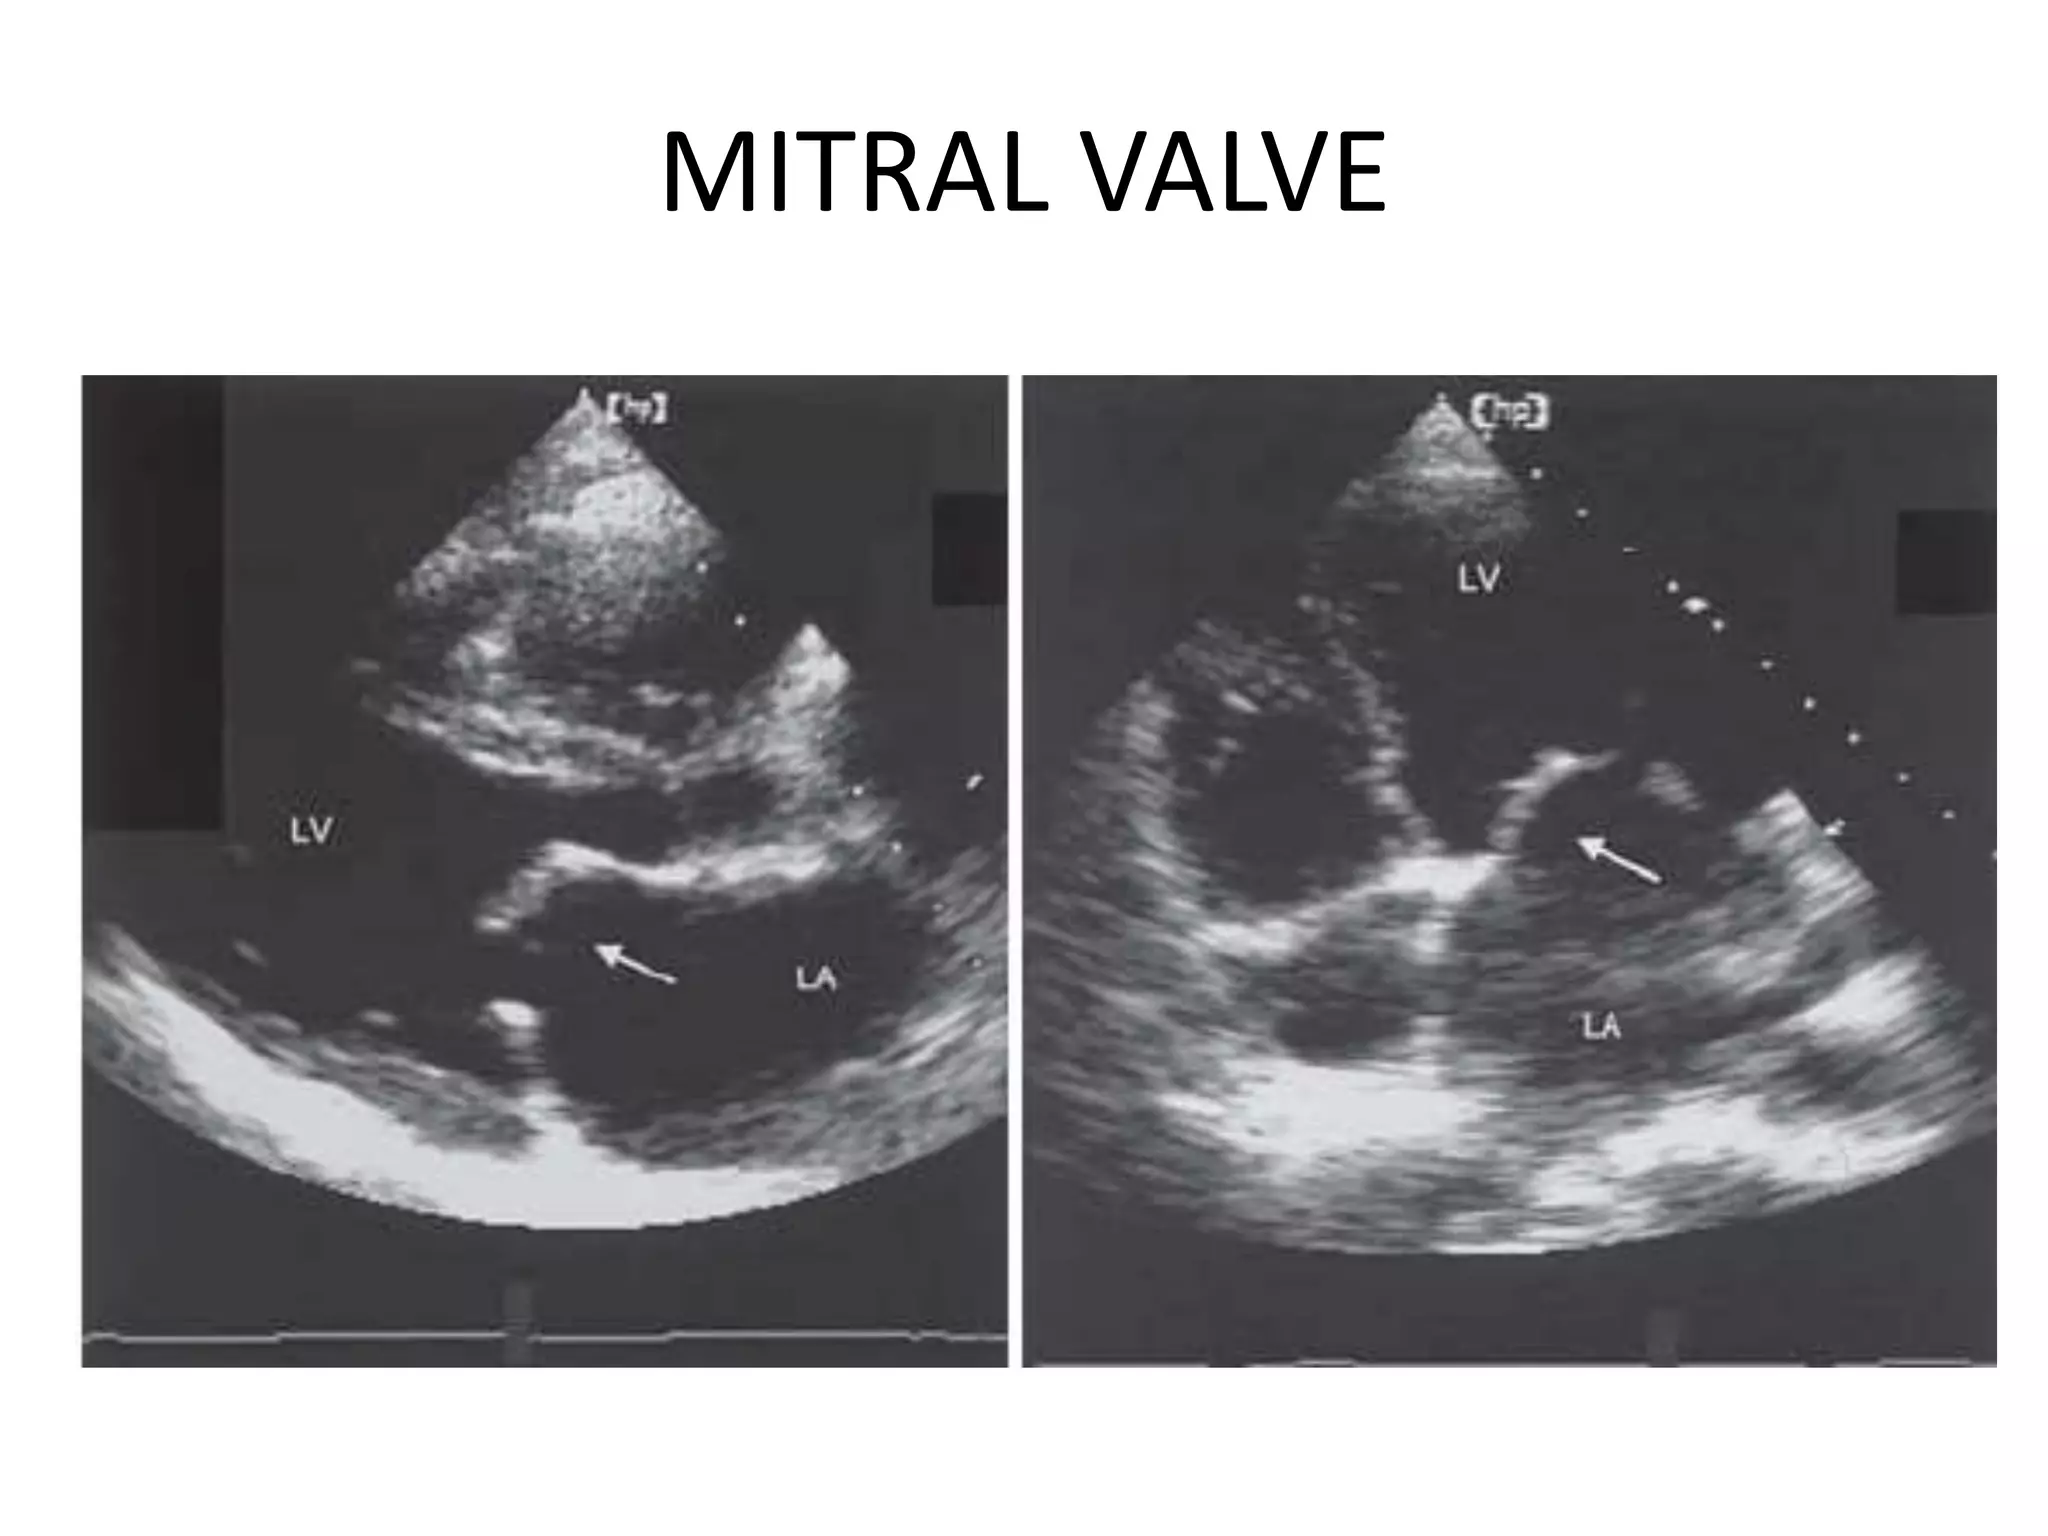

MITRAL VALVE

MS

Changes in MV area with severity of

Normal valve : 4–6 cm2

Mild MS : 2–4 cm2

Moderate MS : 1–2 cm2

Severe MS : <1 cm2.

Criteria for diagnosis of severe

MS (many derived from

Doppler)

• Measured valve orifice area <1 cm2

• Mean pressure gradient >10 mmHg

• Pressure half-time >200 ms

• Pulmonary artery systolic pressure

>35 mmHg.

MS Changes in MVarea with severity of MS Normal valve : 4–6 cm2 Mild MS : 2–4 cm2 Moderate MS : 1–2 cm2 Severe MS : <1 cm2. Criteria for diagnosis of severe MS (many derived from Doppler) • Measured valve orifice area <1 cm2 • Mean pressure gradient >10 mmHg • Pressure half-time >200 ms • Pulmonary artery systolic pressure >35 mmHg.